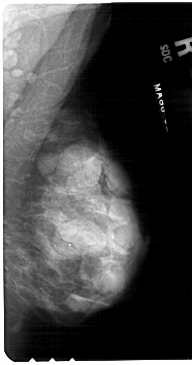

A_1484_1.RIGHT_MLO

RIGHT_MLO LINES 5461 PIXELS_PER_LINE 2866 BITS_PER_PIXEL 12 RESOLUTION 43.5 NON_OVERLAY